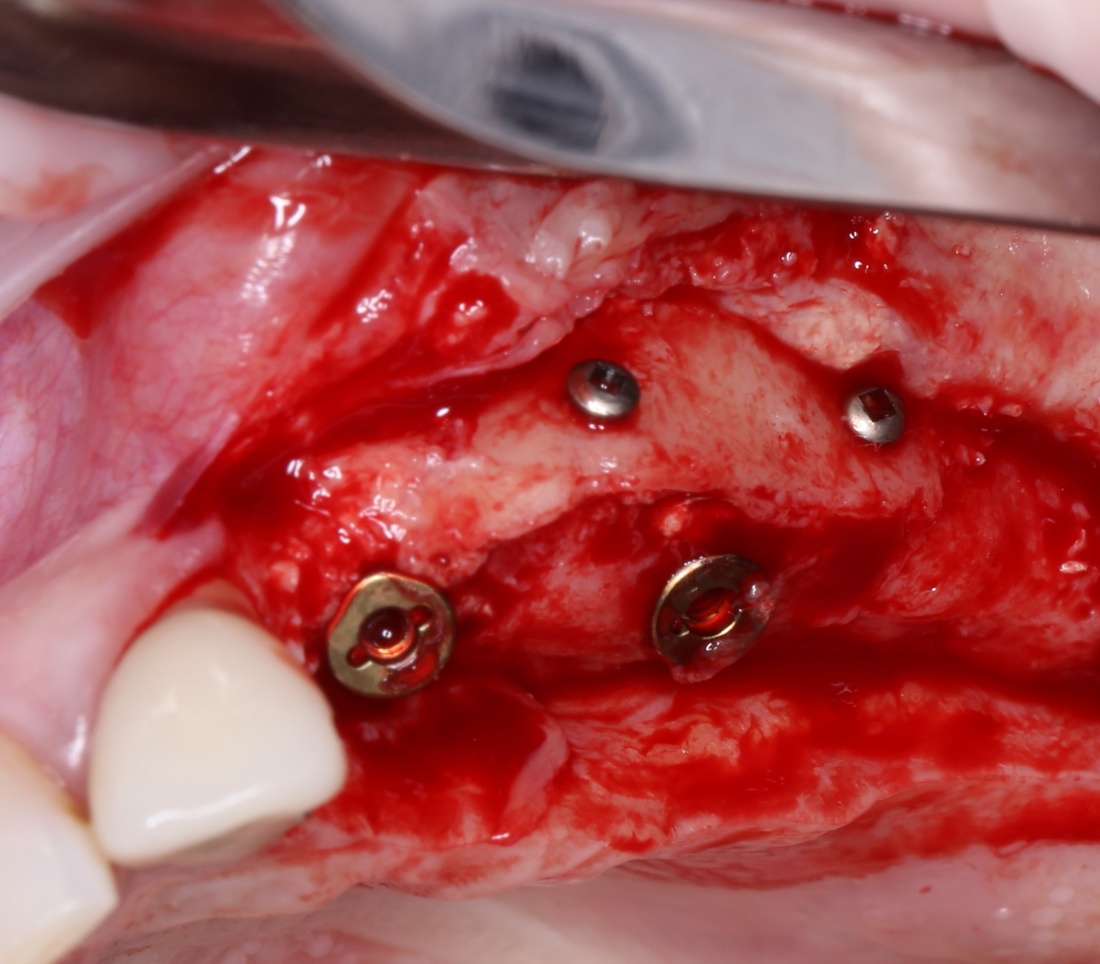

Итак, мы удаляем клык, по шаблону устанавливаем импланты, строим «каркас» будущего альвеолярного гребня в области пятерки:

Для синуслифтинга мы используем Geistlich Bio-Oss, который пригодился нам как для остеопластики (наполнения построенного «каркаса»), так и для аугментации лунки: